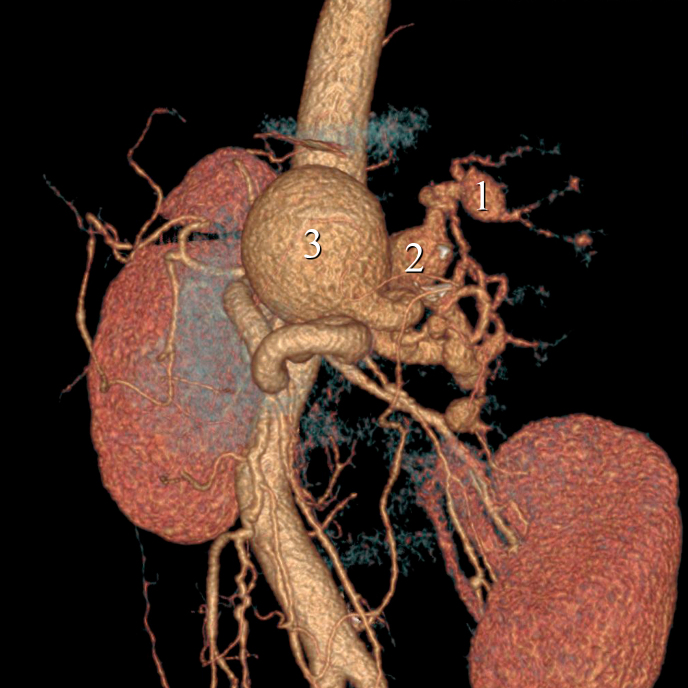

脾动脉瘤是第三种最常见的腹内动脉瘤,也是最常见的内脏动脉瘤。门静脉高压是这类动脉瘤发病的重要危险因素。我们报告了一例 52 岁的白人女性患者,她患有多发性脾动脉瘤和脾功能亢进,继发于门静脉高压症和肝硬化。腹部血管造影发现了六个脾动脉瘤。在这种情况下,安排了一次血管内介入治疗,使用控释线圈和Onyx™栓塞剂进行栓塞。三个最大的动脉瘤得到了治疗。对照血管造影显示动脉瘤排除良好。因此,考虑到患者的合并症和血液疾病,血管内技术被证明是一个不错的选择。在这个病例中,手术非常成功。没有出现即刻或长期并发症。患者恢复良好,目前正在接受临床随访。

Aneurysms of the splenic artery are the third most common type of intra-abdominal aneurysms and the most common type of visceral aneurysms. Portal hypertension is a significant risk factor for development of these aneurysms. We report the case of a white, female, 52-year-old patient with multiple splenic artery aneurysms and hypersplenism secondary to portal hypertension and cirrhosis. Abdominal angiotomography identified six splenic aneurysms. In this scenario, an endovascular intervention was scheduled to conduct embolization using controlled release coils and Onyx™ embolization agent. The three largest aneurysms were treated. Control angiographs showed good exclusion of the aneurysms. The endovascular technique therefore proved to be a good choice considering the patient's comorbidities and blood disorders. In this case, the procedure was successful. There were no immediate or long-term complications. The patient recovered well and is in clinical follow-up.